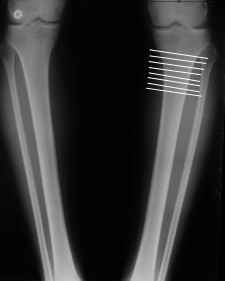

Вот ещё картинки, которые отправлял в Ортопод. Коррекция кривизны и удлинение на 3 см.

Снимки в приложении - фас сравнительный с неоперированной ногой. Жду критики.

Впрос про остеотомию большеберцовой непраздный. Эта получилась при надломе несколько более наклонно, чем я делал (сейчас проблема,

как на второй ноге сделать так же). Вот этот высоящий "зуб" центрального отломка не заменит ли в плане косметики то, что получается при медиализации дистального?

The analysis in the attached images is direct, just using the tools.

Tibial tilt is perhaps more than you want but the tibial correction is to 90 (very slight over

correction.

Will need full length views to tell us about the hka but it appears neutral.

Measurements took 4 mins